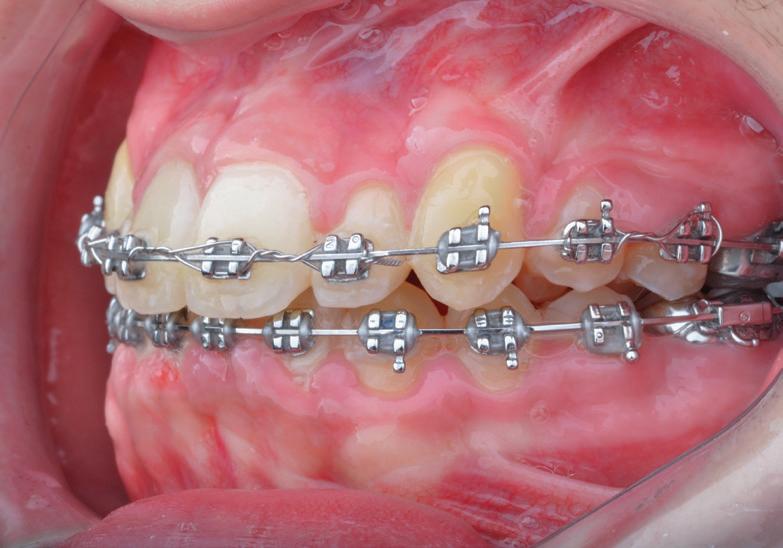

Pentru tracționarea dinților impactați, este importantă utilizarea fie a unui arc de sârmă cu bază dreptunghiulară din oțel inoxidabil, fie o bară transpalatinală groasă, cu rigiditate adecvată. Acest lucru este esențial în special la caninii incluși palatinal. Evitarea utilizării arcurilor flexibile poate permite un control mai bun al efectelor adverse asupra dinților adiacenți în timpul tracțiunii. Se poate obține o ancorare suficientă în interiorul arcadei, prelucrând secvența până la arcurile 0,019 x 0,025 într-un slot de 0,022. Acest lucru previne deformarea arcurilor, deschiderea ocluziei din cauza tracțiunii, intruziunea dinților adiacenți și alte efecte adverse conexe. S-au utilizat diferite elemente externe, cum ar fi porțile batante, arcurile transpalatinale, extensoarele Hass, arcurile guad helix, expansoarele Hyrax și dispozitivele de ancorare temporară (temporary anchorage devices, TAD), ca aparate de ancorare alternative. În cazul unei bare transpalatinale, obiectivul este de a utiliza brațele de extensie în consolă pentru a tracționa caninul impactat în palat. Aceasta este urmată de tracțiunea caninului în poziția sa finală, utilizând arcuri de poziționare sau alte metode pentru a aduce dintele inclus pe arcada dentară (fig. 4, 5).

Considerente în timpul activării caninilor incluși

Trebuie să se aplice vectori de forță care să permită mobilizarea caninului dinspre rădăcina dinților

adiacenți, în special în cazurile cu o relație strânsă între canin și incisivul lateral. Caninii impactați foarte profund palatinal ar trebui să fie activați mai întâi ocluzal și, în multe cazuri, distal, înainte de a fi mutați în poziția dorită pe arcadă. Pot fi utilizate elemente auxiliare, precum lanțurile elastice, filetul elastic, bobinele de nichel-titan, arcurile de extruzie auxiliare, buclele baliste, brațele în consolă și TAD-urile. Atunci când se suspectează anchiloză, forța de tracțiune trebuie redusă, iar pacientul îndrumat către parodontolog. În astfel de cazuri, se recomandă o radiografie periapicală pentru a determina prezența țesutului osteoid, și a se asigura că țesutul parodontal urmează dintele în cursul deplasării sale.